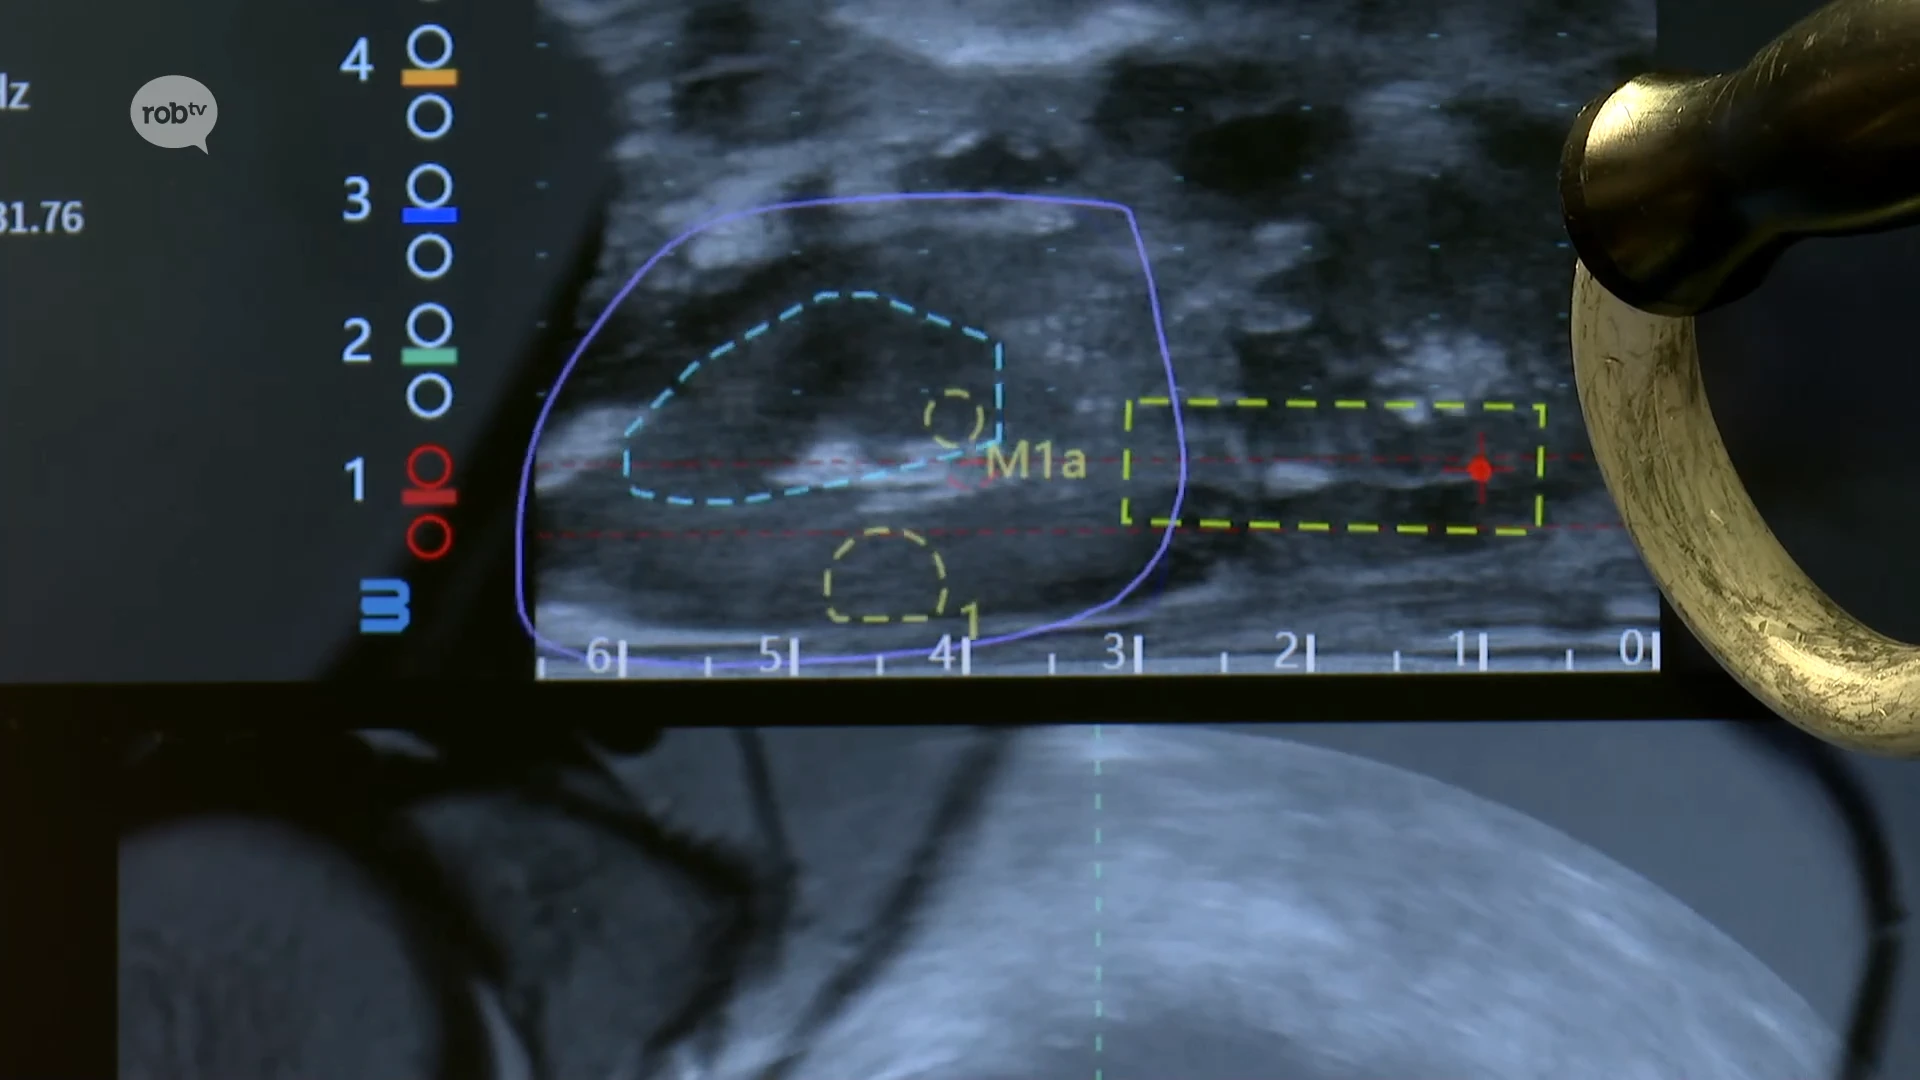

In het Regionaal Ziekenhuis van Tienen is vandaag de eerste prostaatbiopsie uitgevoerd door middel van de Carbon Venustechniek en dat is een primeur in Noord-Europa.

Het gaat om een techniek waarbij artificiële intelligentie verdachte plekken op de prostaat aanduidt en de uroloog visueel helpt bij het weghalen van een stukje weefsel voor verder onderzoek. Dat moet zorgen voor preciezere diagnoses en de kans op complicaties tijdens biopsies verminderen.

"Verdachte plekken voor prostaatkanker worden niet enkel gedetecteerd door een radioloog, maar worden daarbovenop nog eens worden nagekeken door artificiële intelligentie." Joost Berkers, Uroloog RZ Tienen

"Het gaat ons sowieso helpen om preciezere diagnoses te stellen en de kans op complicaties van biopsies te verminderen, zodat we gewoon veel minder prikken moeten geven en veel gerichter kunnen prikken. Dat is sowieso al een enorme winst." Joost Berkers, Uroloog RZ Tienen